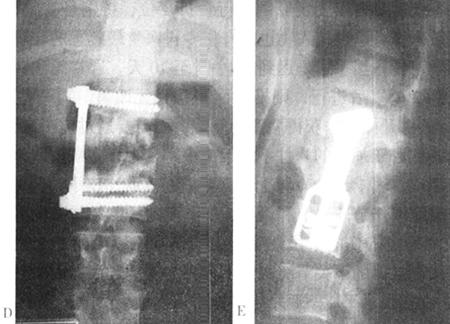

图13-40 25岁男性,被搅拌机搅伤,术前X光片和CT(A、B、C)可见L1骨折脱位,层叠于T12上手术采用右侧前方入路。L1椎体切除后获得复位,大块髂骨植骨和Z-plate Ⅱ内固定

图13-41 28岁女性,T11爆裂骨折,术前侧位片(B)见骨折碎片向后压迫脊髓。前路手术减压,Z-plate Ⅱ固定,使用了钛网。因系统放置在椎体右侧,所以板的头部向下